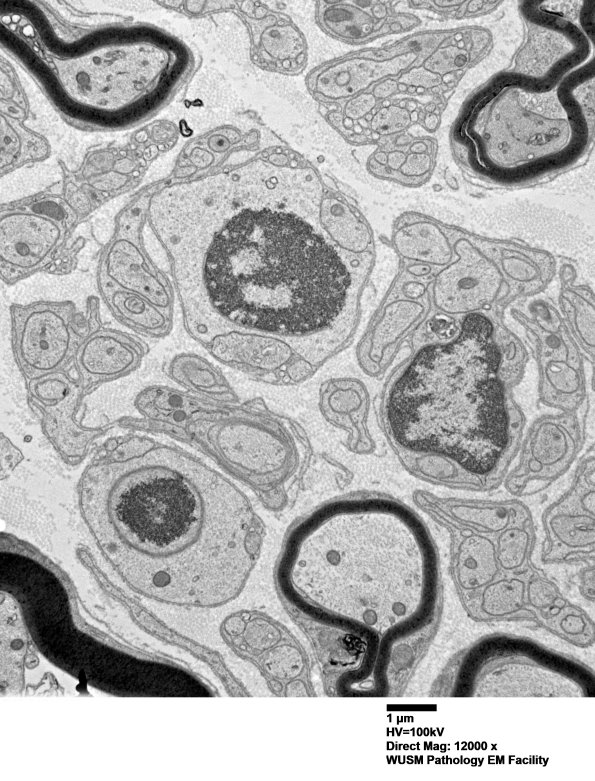

Washington University Experience | PERIPHERAL NEUROPATHY | 1 NORMAL NERVE ANATOMY | 6 Infant Peripheral Nerve | 6B11 (Case 6) EM 027 - Copy

6B11,12 These structures also confuse us. We have considered a variety of entities but tentatively thought these were degenerating Schwann cell nuclei. Notice the area of 6B12 that the granular nucleus is surrounded by a tubular structure with ribosomes on the external leaflet (arrow, 6B12) and a possible nuclear pore (arrowhead, 6B12). (electron micrographs)